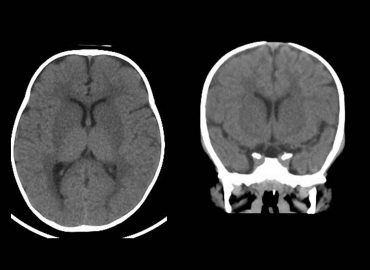

Paciente: femenina de 9 meses de edad Motivo de consulta: episodios convulsivos.